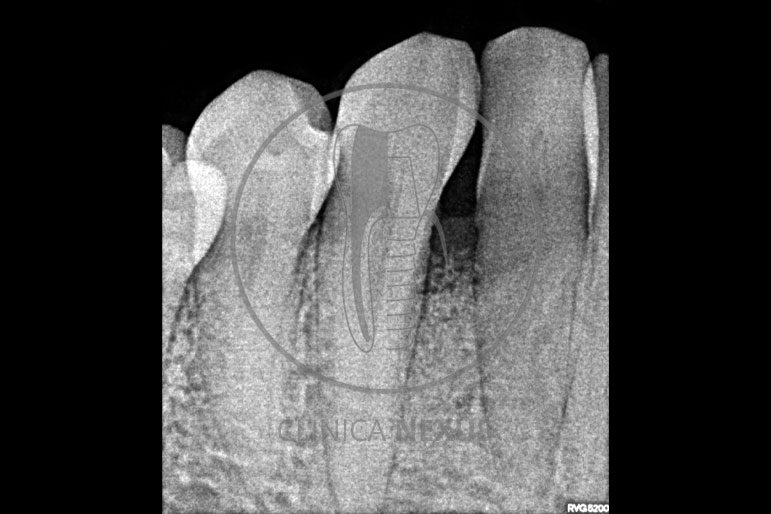

Tratamiento de defectos periodontales infraóseos en sector antero-inferior empleando gel de amelogeninas (Emdogain®) en combinación con un aloinjerto óseo (Biobank®). Paciente de 64 años, sin problemas médicos de relevancia, que presenta una periodontitis leve generalizada, pero asociada a presencia de defectos óseos verticales profundos a nivel de los espacios interdentales entre los caninos y los incisivos laterales inferiores. Tras la pertinente fase higiénica, se llevó a cabo una cirugía periodontal regenerativa, en la que, tras eliminar el cálculo subgingival (factor causal), se empleó una combinación de amelogeninas con un aloinjerto, para promover la regeneración tisular del periodonto perdido. Las imágenes clínicas y radiológicas, al año de seguimiento, reflejan un resultado terapéutico óptimo, con regeneración completa del tejido periodontal y mejora del pronóstico de los dientes involucrados.